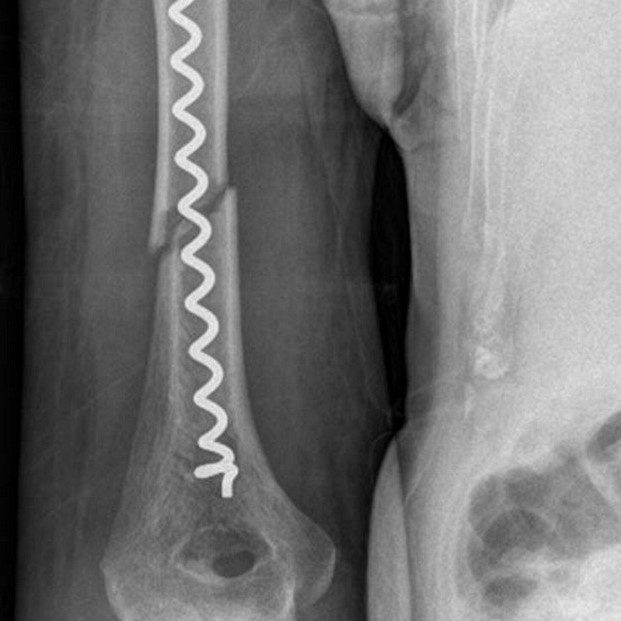

Dr. Senat Krasnici, Chefarzt der Klinik für Unfall- und Wiederherstellungschirurgie des Johanniter-Krankenhauses Genthin-Stendal, berichtet über seine Erfahrungen mit der Bonehelix als limitiertflexibler Markraumstabilisator.